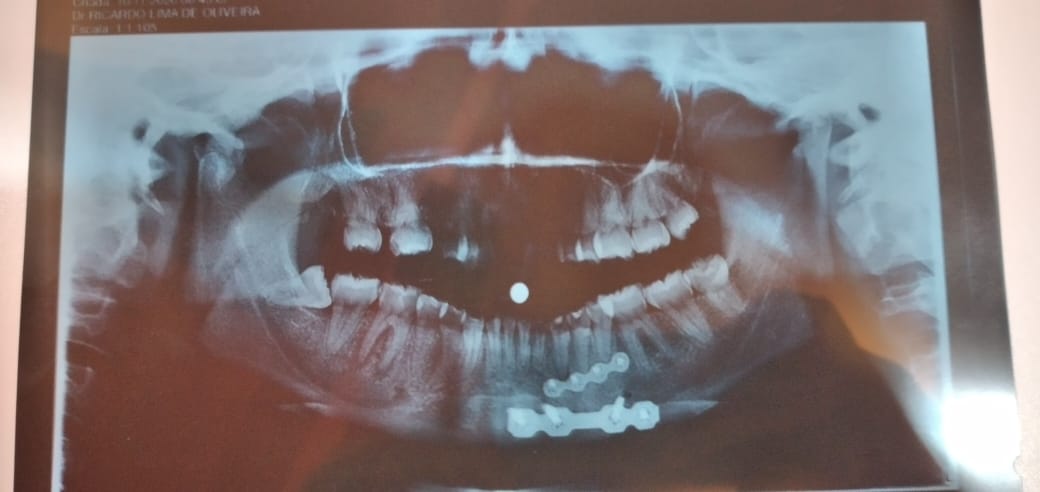

Tendo sido socorrido para o Hospital Regional de Patos, ela passou 10 dias internadas. Ela quebrou a mandíbula. Foi feito uma cirurgia e após o décimo segundo dia ela retornou para casa, onde teve complicações. Infecções fizeram da vida de Ludmila um verdadeiro sofrimento.

A placa ficou infeccionada e a jovem agora tem que fazer uma nova cirurgia, porém por conta dos leitos lotados com casos de Covid-19, precisará desembolsar o valor de R$ 4mil para o tratamento um ano e cinco meses após o acidente em uma clínica particular. Manchas vermelhas surgem por todo o corpo da jovem.

A mãe conta que a jovem perdeu vários dentes e que foi necessário usar uma prótese. As dificuldades na casa não são apenas com a jovem. A mãe dela perdeu completamente a visão e Ludmila se tornou uma aliada nos serviços da casa.